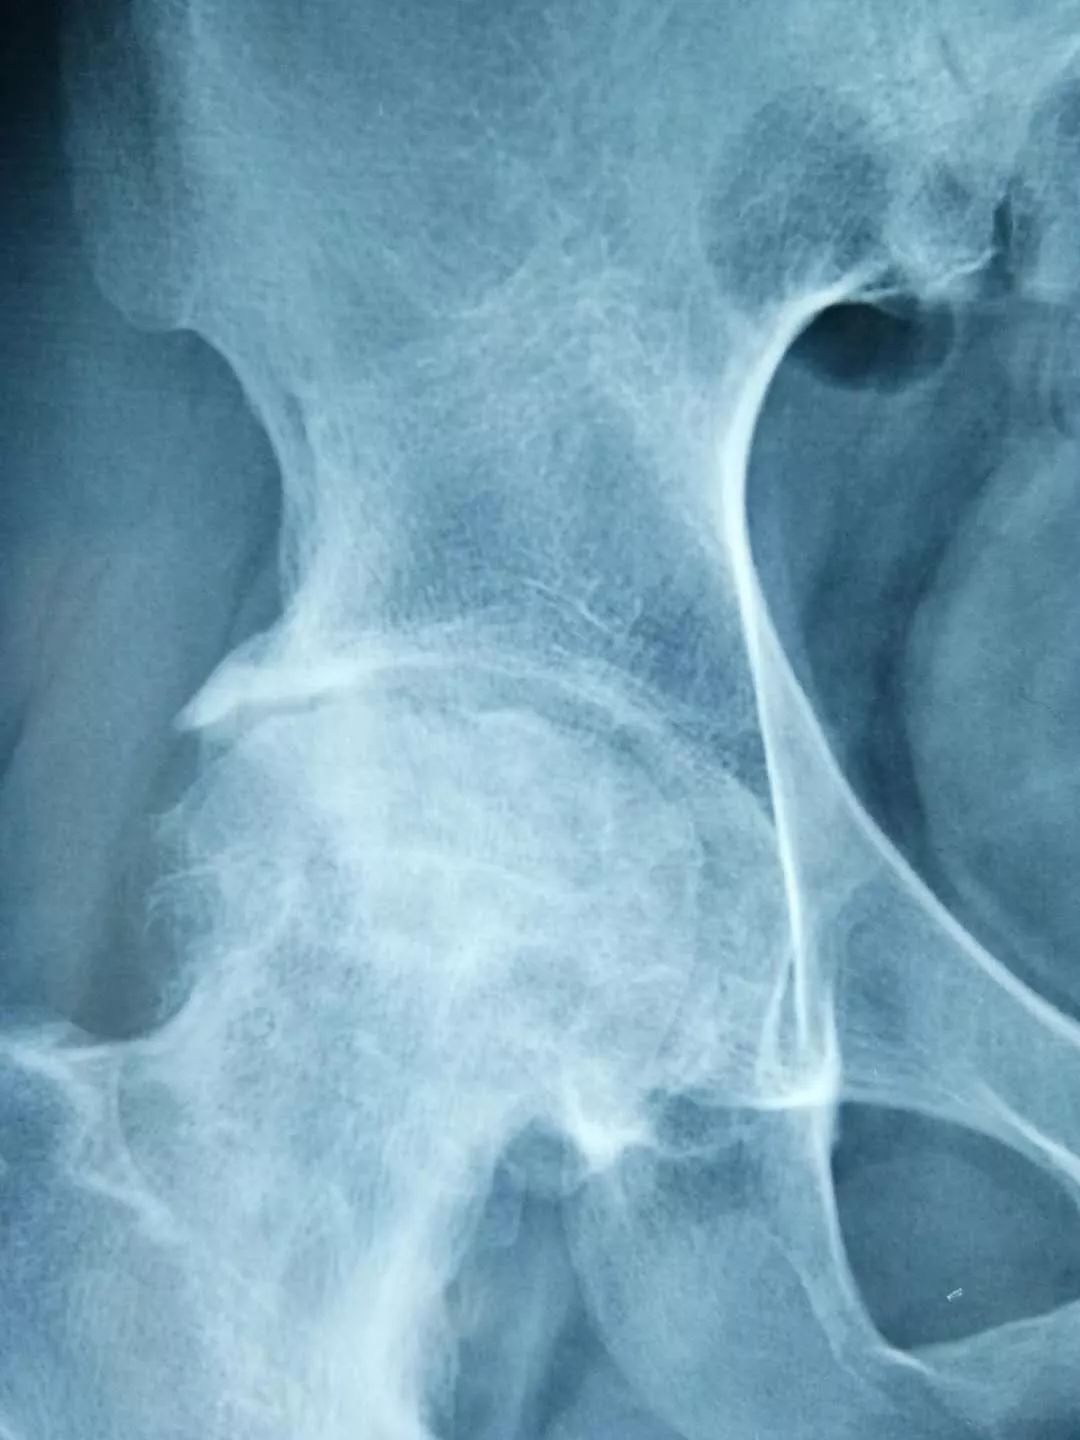

青岛患者张先生50岁出头就患上了双侧股骨头坏死,病程3期,多个医院给出的治疗方案均是置换人工关节,张先生不能接受,经人介绍找到廉从希。廉从希以红花、人参、鹿茸、阿胶、当归等生血散寒、除湿祛瘀的中药配伍令其内服,以马钱子、川乌、秦艽、元胡、透骨草、土元等20余味道地药材炼制成膏药令其外敷,并结合切肤骨蒸方法令疗效最大吸收。一个疗程后患者症状便明显好转,坚持治疗3个月后去医院检查,股骨头坏死症状完全康复。

一名*安泰**的女性股骨头坏死患者,在儿女强力怂恿下来淄博找廉从希求医,一开始对“廉氏三联疗法”并不抱太大信心,但一个疗程结束后,患者便惊喜地发来医院检查的骨片,股骨头坏死部位纹理已明显开始致密均匀,病情有了很大好转。患者自此坚定了治疗信心,持续治疗3个月后痊愈。

经对118名患者跟踪调查,“廉氏三联疗法”对股骨头坏死的总有效率在92%以上;显效率(症状明显好转,功能障碍恢复)87%以上;病理改善率(影像显示骨密度增强)83%以上;临床治愈率(观察一年以上,症状消失,功能障碍恢复,可做日常家务及轻体力劳动)75%。

左图为治疗前,右图为治疗后。